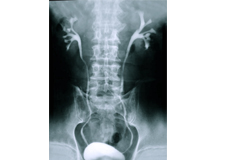

Cystoscopy with Retrograde Pyelogram

A retrograde pyelogram is a type of X-ray that allows visualization of the bladder, ureters, and renal pelvis. During a cystoscopy, contrast dye, which helps enhance the X-ray images, can be introduced into the ureters via a catheter.